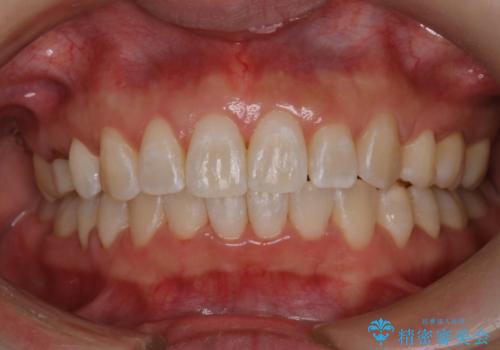

- インビザラインで非抜歯治療を行いました。IPRと拡大をし、叢生、咬合をきれいにしました。

主訴であったかみ合わせを正しい位置に動かし、バランスよくかめるようになりました。矯正治療終了後にメタルインレーをセラミックインレーに替えました。